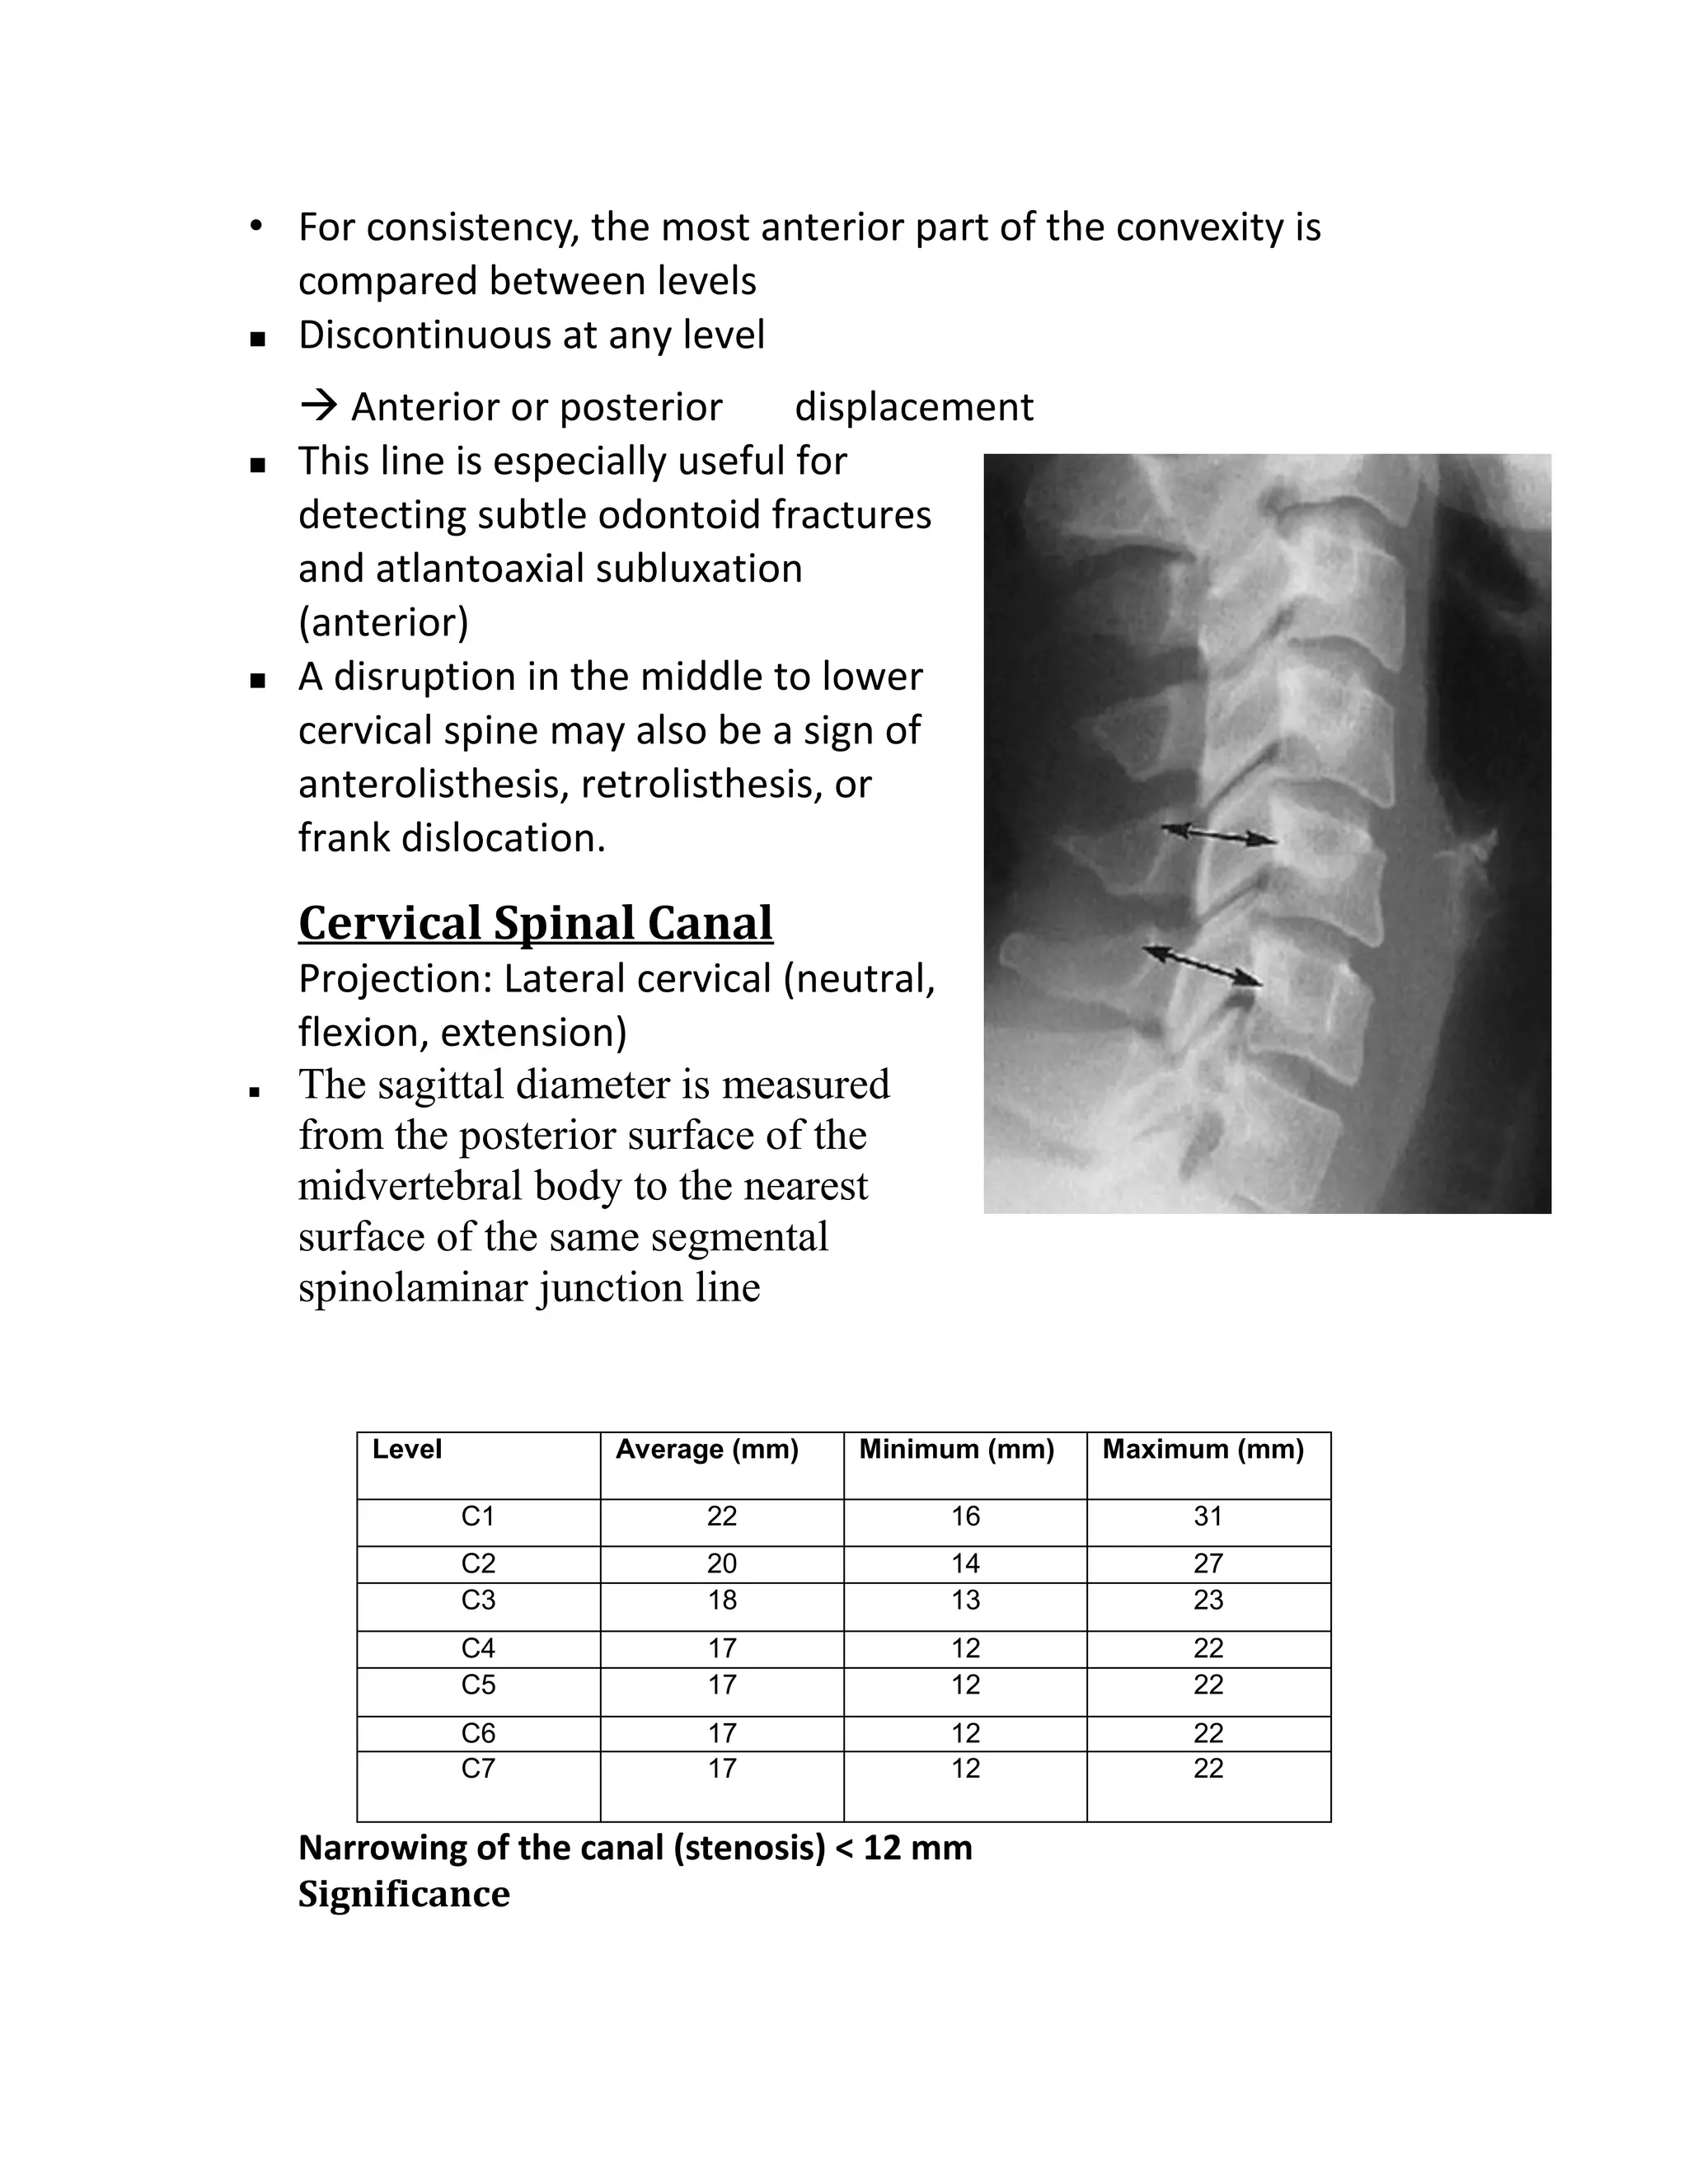

Spinolaminar junction line

Posterior Cervical Line, arch-body line.

 Projection: Lateral cervical spine

(neutral, flexion, extension).

 The cortical white line of the

spinolaminar junction identified at

each level C1 to C7

• Each spinolaminar junction will be

curved slightly anteriorly from

superior to inferior

• For consistency, the most anterior part of the convexity is

compared between levels

 Discontinuous at any level

 Anterior or posterior        displacement

   This line is especially useful for

detecting subtle odontoid fractures

and atlantoaxial subluxation

(anterior)

   A disruption in the middle to lower

cervical spine may also be a sign of

anterolisthesis, retrolisthesis, or

frank dislocation.

Cervical Spinal Canal

Projection: Lateral cervical (neutral,

flexion, extension)

   The sagittal diameter is measured

from the posterior surface of the

midvertebral body to the nearest

surface of the same segmental

Level          Average (mm)   Minimum (mm)   Maximum (mm)

C1          22               16           31

C2          20               14           27

C3          18               13           23

C4          17               12           22

C5          17               12           22

C6          17               12           22

C7          17               12           22

Narrowing of the canal (stenosis) < 12 mm

Significance